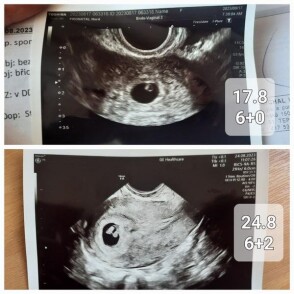

Dobrý den paní doktorko, jsem momentálně těhotná (mám za sebou jedno zamlklé těhotenství, miminko je opravdu vymodlené). První ultrazvuk byl 17.8 (dle ms mělo být 6+3) a pan doktor v CAR vypočítal těhotenství na 6+0 s AS, což není nic zvláštního, protože vzhledem k PCOS mívám ovulaci opravdu později. Vzhledem k tomu, že pracuji v nemocnici a stal se mi tam takový malý úraz (uklouzla jsem) tak se mi hned pan doktor nabídl, že uděláme kontrolní ultrazvuk (tudíž jiný lékař, jiný ultraz.přístroj). Vyděšil mě když těhotenství vypočítal jen na 6+2 místo 7+0 (bylo to po týdnu). Akce srdeční byla stále..jen mám strach, že se opravdu začíná opožďovat ve vývoji a znovu mě potká zamlklé těhotenství. Přikládám foto z obou ultrazvuků. Připadá mi i laickým okem, že embryo rozhodně větší je. Je možné, že to pan doktor špatně změřl? nebo že každý přístroj měří jinak?Děkuji vám !

Dobrý den, teď je otázka, která struktura byla měřená, zda EES (časná délka embrya) - mluvit o CRL je v tomto týdnu brzy.. nebo např. průměr gestačního váčku.. takto se dle fotky momentálně nejeví nic dramaticky špatně, proto bych vyčkala do další kontroly, v těchto nižších týdnech může být ta velikost taková variabilní a nelze pominout i možnost nepřesného měření. Držím palce!